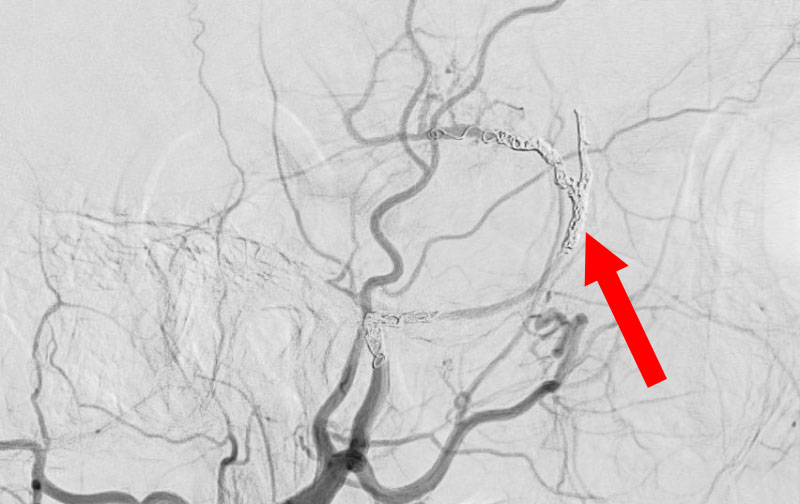

1598

'25年11月26日

右円蓋部髄膜腫

40代

大阪府の病院

治療

中